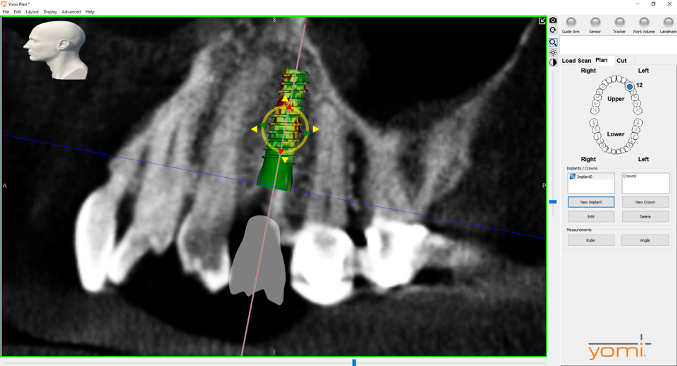

(4.) Digital plan of the virtual implant.

Figure 4

(5.) Digital plan of the virtual implant.

Figure 5